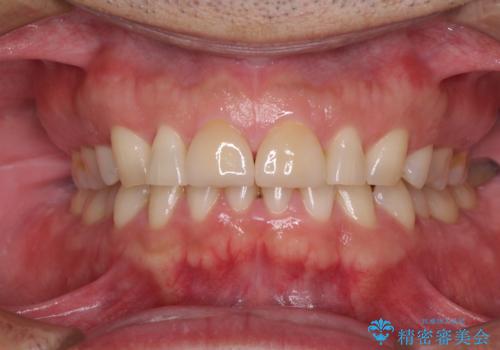

ラミネートベニアは切削量が少ないことがメリットとしてあげられますが、色調を周辺と合わせられないこと、接着境界線が長く汚れや歯石が溜まりやすいことがデメリットとして考えられます。

また、接着境界線にむし歯がある場合には適用外となるなど、適用症例を選ぶため、治療に際して担当医としっかりと相談することが大切です。